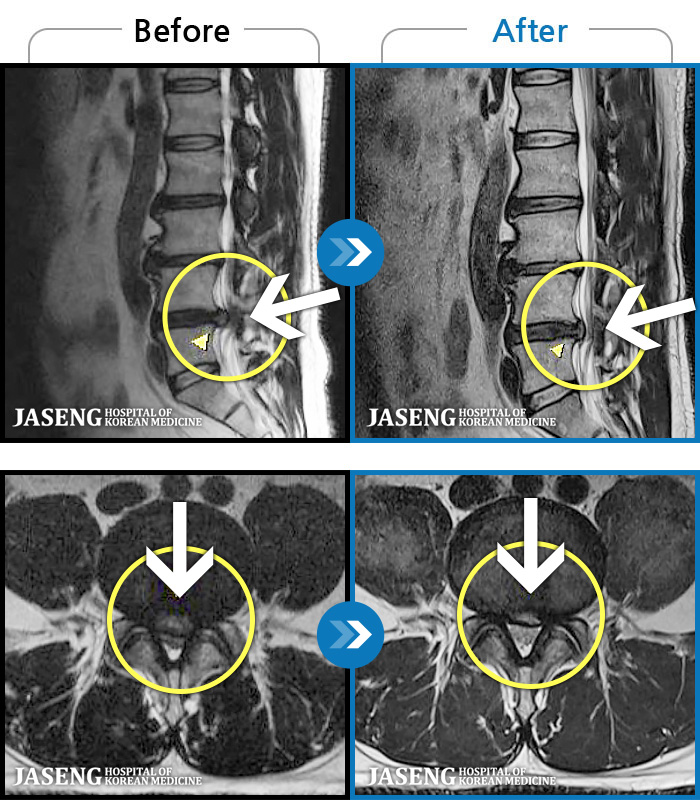

Before

After

환자에게 사전 동의를 받아 동일 조건에서 촬영되었습니다.

개인에 따라 치료 후 부작용이 발생할 수 있으니 의료진과 상담 후 치료를 진행하시기 바랍니다.

심한 허리 통증으로 내원

우측 골반 통증이 심하고 우측 하지로 당김과 저림이 지속되었습니다. 야간통이 심하여 야간 수면 제한이 되는 등 중등도 이상의 통증을 호소하는 상태였습니다.